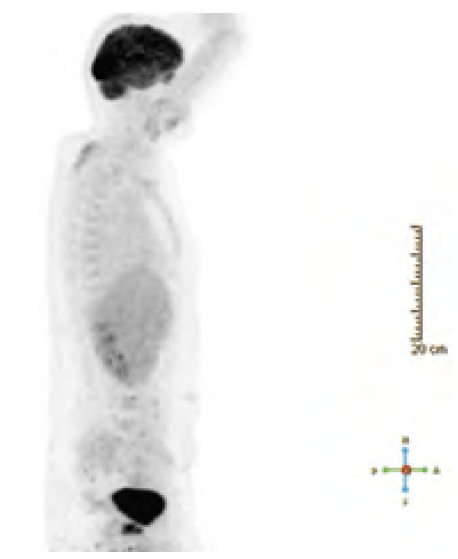

CT-Thorax/Abdomen: kein Anhalt für eine thorakoabdominelle Metastasierung. PET-CT: Hypermetabolismus der infravesikalen Formation, vereinbar mit malignem Prozess. Keine FDP-positiven Lymphknoten- oder Fernmetastasen (siehe Abbildung 2)